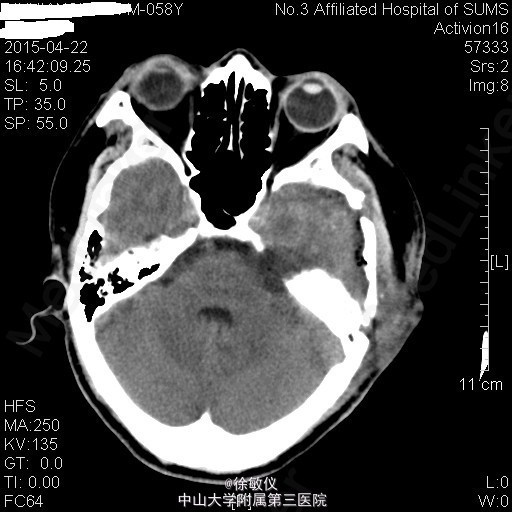

老年患者,主诉:左耳耳鸣、听力下降8年,伴头痛2个月。 现病史:患者8年前始无明显诱因反复出现左耳耳鸣,自诉如鞭炮样鸣响,伴听力进行性下降,无耳道流血流液,可自行缓解。患者曾至当地医院就诊,保守治疗后改善不明显。2个月前始患者出现阵发性全头痛,偶伴头晕、恶心,近2周呕吐胃内容物2次,无发热,无肢体活动异常等不适。于当地医院行头部CT,结果提示:左侧桥小脑角区占位性病变伴出血,听神经瘤(神经鞘瘤)可能性大。患者为进一步治疗来我院。

查体:左耳听力缺失,右耳听力正常。余查体无特殊。 辅查:头部MR:1、左侧桥小脑角区占位病变,考虑为听神经瘤并出血、囊变,病变与左侧听神经、椎动脉关系密切;2、颅脑MRA示脑动脉未见异常。 头部CT:双侧额顶枕叶、半卵圆中心、侧脑室周围、放射冠、基底节区及右侧岛叶多发密度灶,考虑缺血变性灶;颅脑CTA示肿瘤与左侧椎动脉关系密切。

排除手术禁忌后于2015-04-03在全麻下行左侧桥小脑角区占位病变+脑室侧引流+颅内压探头植入术,术程顺利。术后于SICU监护生命体征平稳后转入我科,予预防感染、抑酸、营养支持及对症治疗,患者恢复良好。 术后复查头部CT未见明显异常。 病理诊断:(桥小脑角占位)符合富于细胞性神经鞘瘤。